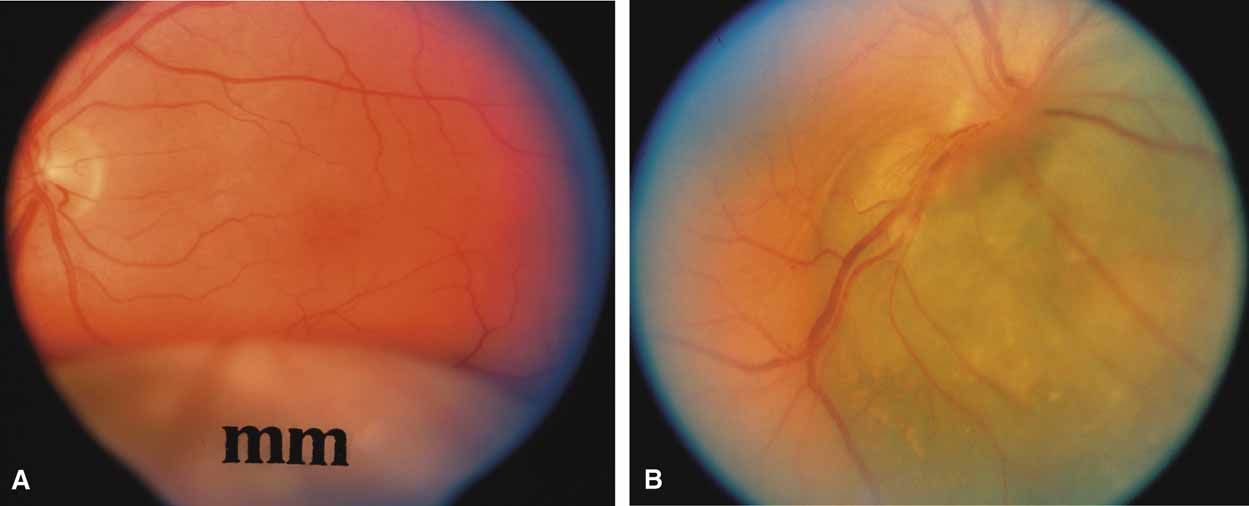

The majority of cases of ghost cell glaucoma occur following vitrectomy for diabetic retinopathy, vitreous hemorrhage due to trauma, or vitreous hemorrhage following anterior segment surgery (i.e., cataract extraction or corneal transplant). Although studies suggest that a disruption of the anterior hyaloid face may be a necessary precedent, ghost cell glaucoma probably can occur with an intact hyaloid if a sufficient quantity of vitreous blood is present.27 The clinical presentation includes acute pressure elevation, corneal edema, and lack of keratic precipitates. Minute tan cells (ghost cells) may layer out, producing a pseudohypopyon or, if admixed with blood, a “candy-striped” hypopyon. (Fig. 3) Intraocular pressure elevations after diabetic vitrectomy raise concerns regarding concomitant neovascular glaucoma. However, neovascular glaucoma rarely develops in the immediate postvitrectomy period, unless some anterior segment neovascularization was present preoperatively. Late-onset pressure elevations (> 6 to 8 weeks out) in a postvitrectomized diabetic eye usually signal neovascular glaucoma.